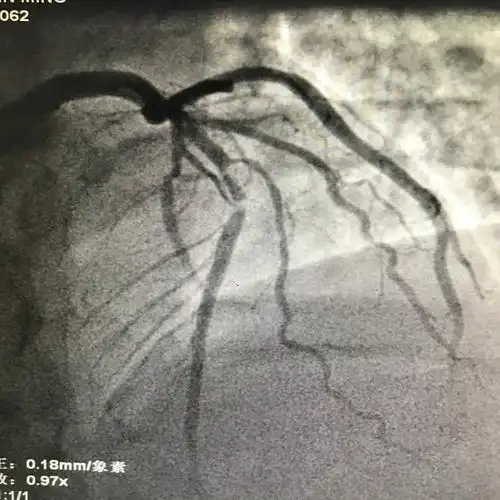

前降支中段两处病变狭窄60-90%.